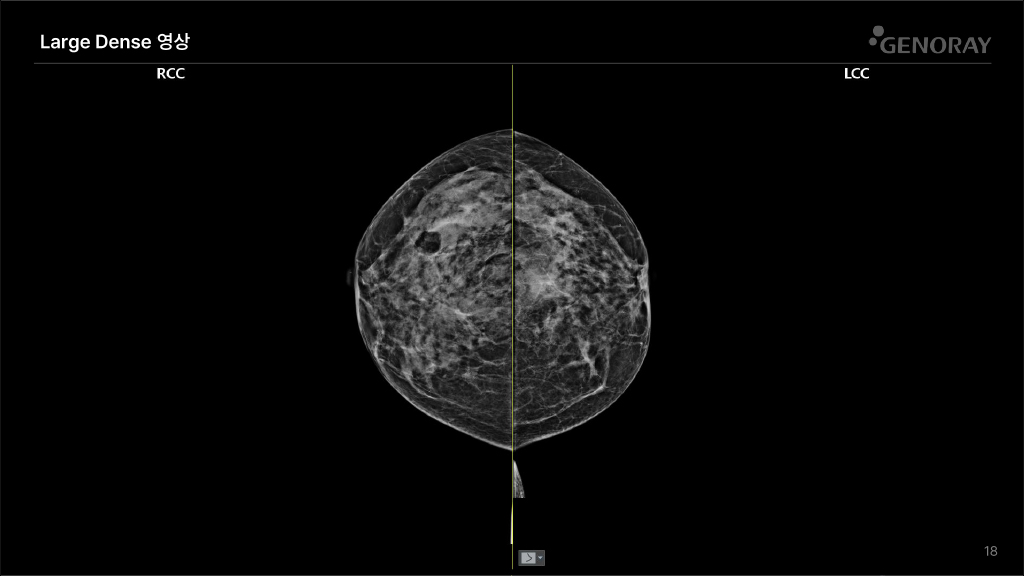

CLINICAL IMAGES

오랜 경험을 통해 축적된 노하우로 진단영상을 제공합니다.